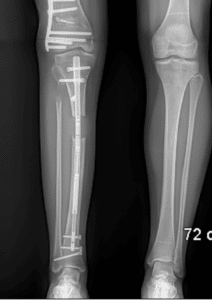

The femur (thigh bone) is the most commonly lengthened bone with internal nails. This can also be done to the tibia (shin bone) and the humerus (upper arm bone) (Fig 1).

Fig 1: Left – Bilateral femoral lengthening nails. Center – Right tibial lengthening nail. Right – Right humeral lengthening nail